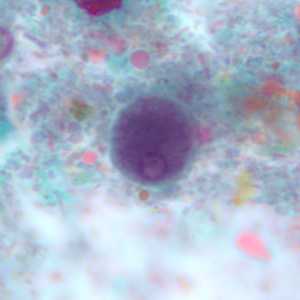

I. buetschlii trophozoite stained with trichrome.

Figure A: Trophozoite of I. buetschlii stained with trichrome.

Figure B: Trophozoite of I. buetschlii stained with trichrome.